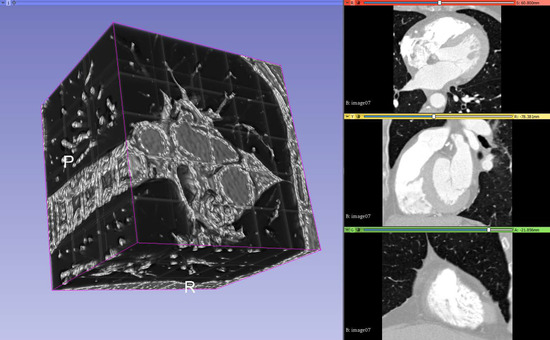

4.2. Visualization

A 3D slicer (available from [33]) is a free and open source software platform useful for three-dimensional visualization useful for image-guided therapy (IGT), image processing with registration and interactive segmentation, and medical image informatics. It receives funding support from national health institutes and development support from a large worldwide community of developers with the code available on GitHub (available from [34]). It is directed by National Alliance for Medical Image Computing (NA-MIC), the Neuroimage Analysis Center (NAC), the National Center for Image-Guided Therapy (NCIGT), etc.

The code compiles cross-platform and it is extensible via plug-ins for different algorithms and applications. It supports python scripting for the customization of the look and workflow.

It supports loading DICOM file format for different types of images such as CT, MRI, nuclear medicine, and microscopy. For usage, it contains functionality supported through modules for different organs and contains a bidirectional interface for integration with medical devices.

A 3D Slicer works with scenes, which are a list of elements to be loaded such as images, volumes, models, transforms, fiducial markers. Element extensions include: vtk (Visualization ToolKit), nrrd (Nearly Raw Raster Data), png (Portable Network Graphics), along with the scene file, which is a mrml (Medical Reality Modeling Language); they are archived into a mrb file (Medical Reality Bundle).

Additionally, 3D Slicer provides an out-of-the-box module called volume rendering, used for visually inspect the input volumes, input masks, and output predictions by overlapping them in a 3D space. It provides presets for easy rendering from volumetric images when trying to catch different aspects of the investigation. A “Shift” control allows the user to tamper with the thresholding for rendering features.